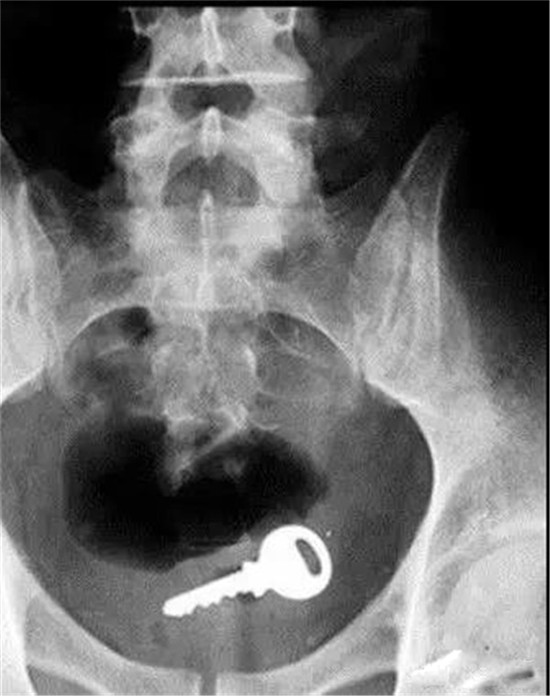

芝麻开门

塞了钥匙进去,难道是要叫肛门芝麻开门?